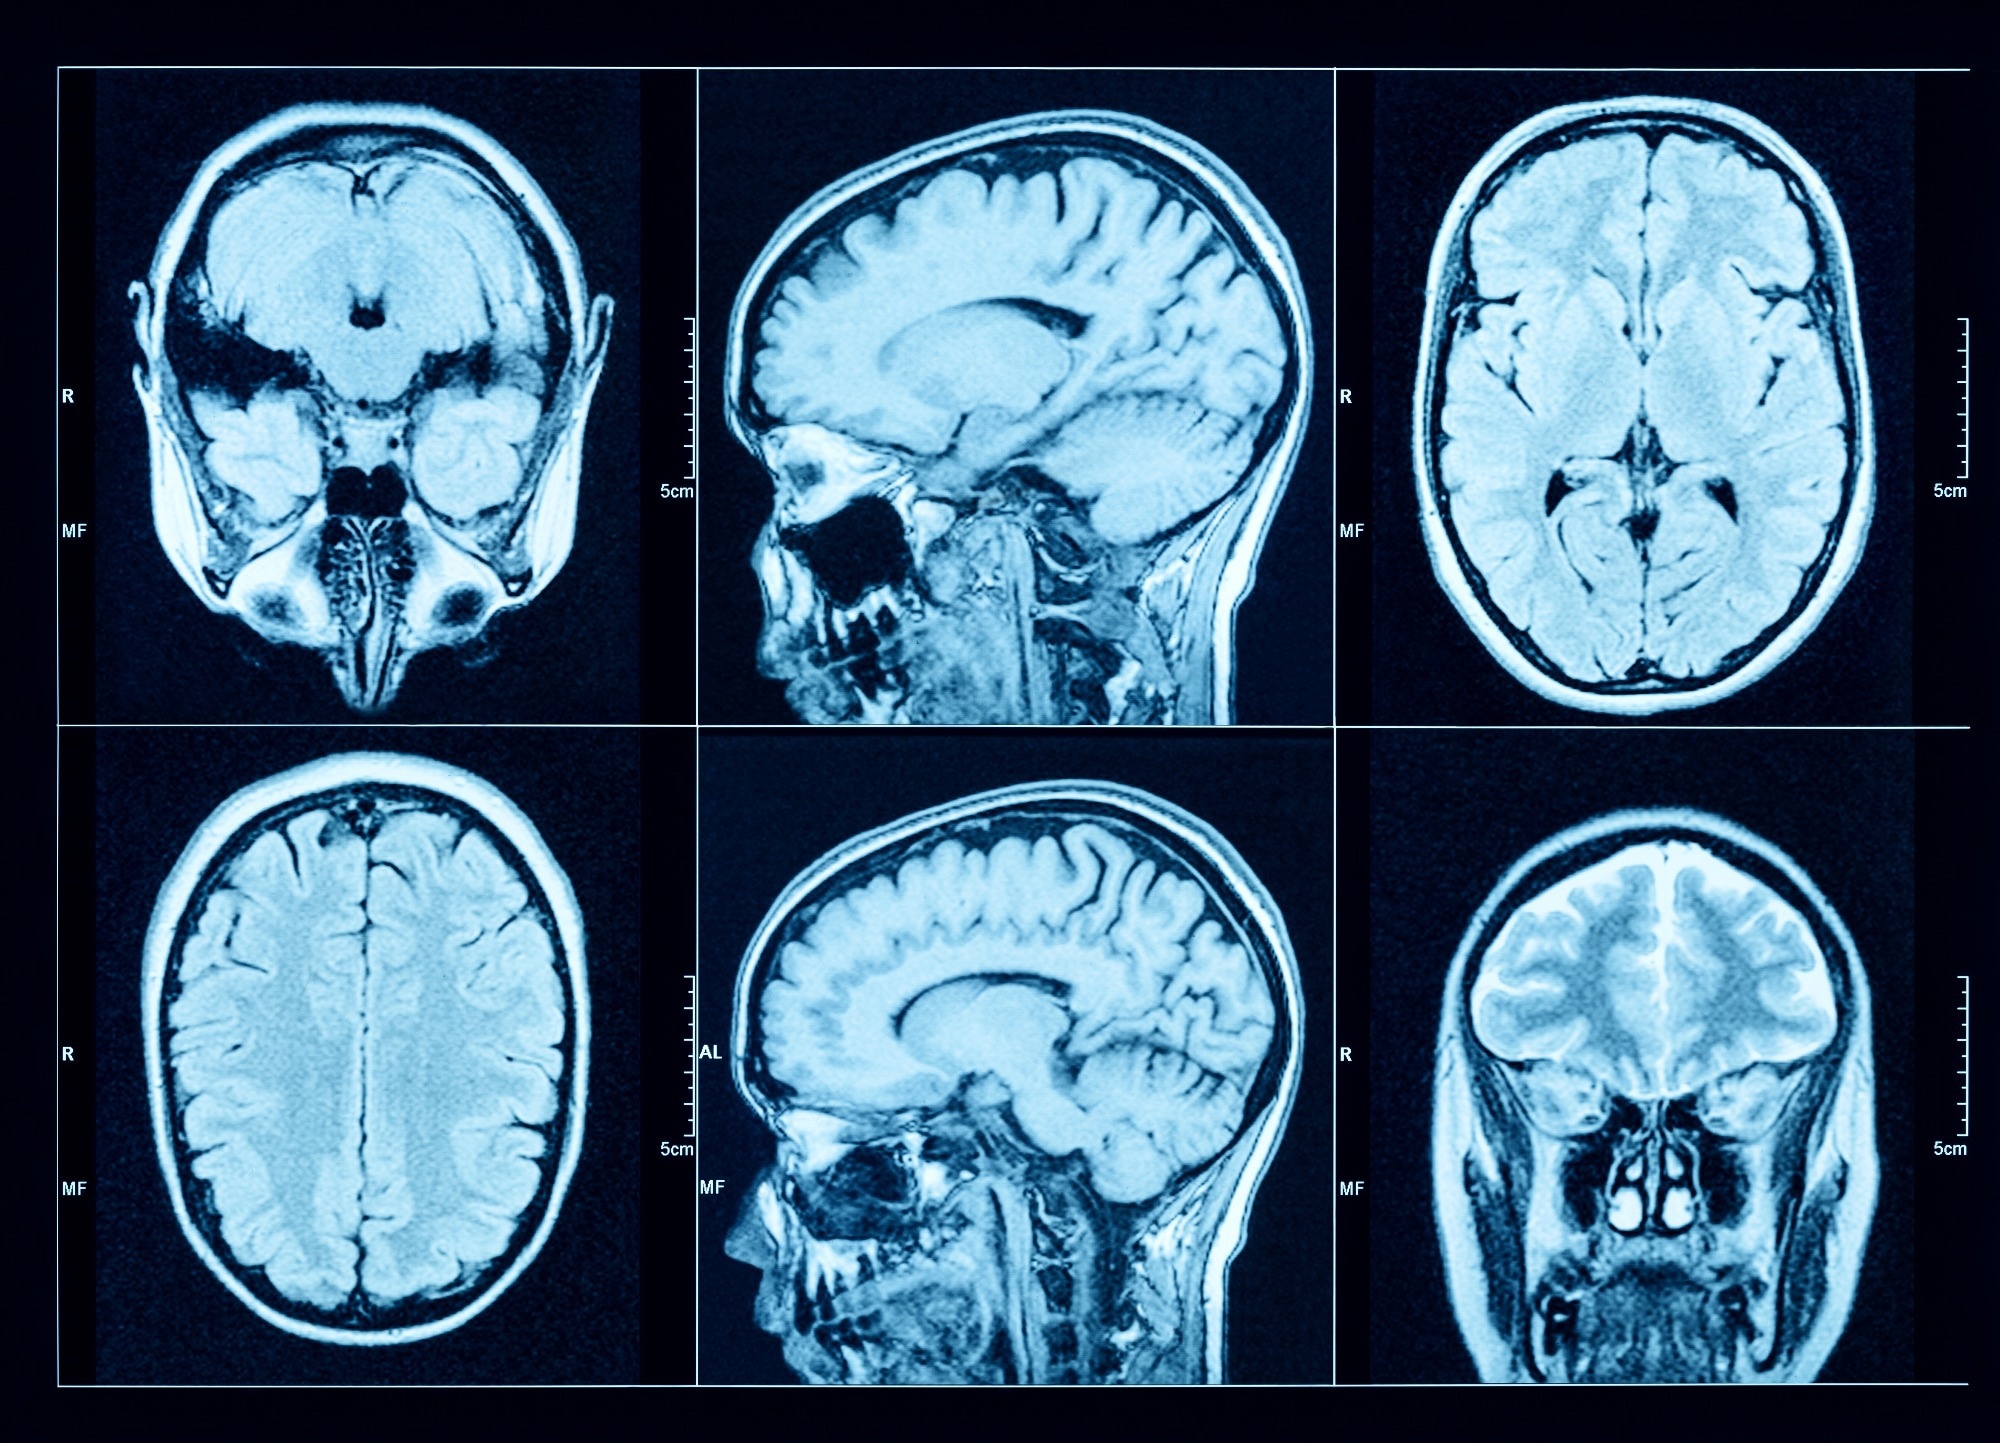

Study: Association of gout with brain reserve and vulnerability to neurodegenerative disease. Image Credit: Triff / Shutterstock.comStudy: Association of gout with brain reserve and vulnerability to neurodegenerative disease. Image Credit: Triff / Shutterstock.com

The team utilized 2,138 summary image-derived phenotypes (IDPs) that represented different estimates of brain structure using T1-weighted and T2-weighted-FLAIR structural imaging, diffusion MRI, and susceptibility-weighted MRI. FMRIB software library voxel-based morphometry (FSL-VBM) was used to determine the precise spatial distribution of relationships between gout and gray matter volume throughout the brain.

MRI results were used to determine whether causal relationships could explain the observed associations with brain structure. One-sample (gout) and two-sample (urate) linear MRI assessments utilizing summary statistics obtained from European participants were also performed.

Urate levels were inversely associated with global brain, grey matter, white matter, and high cerebrospinal fluid volumes. In fact, gout was found to exert the same impact on global grey matter volume as that which is observed when comparing the brain scans of a healthy individual to those of an individual who is two years older.

Some of the specific gray matter regions of the brain that were affected by gout included the cerebellum, pons, and midbrain. Likewise, white matter regions, including the fornix, exhibited higher mean diffusivity and lower fractional anisotropy in gout patients.

The current study is the first of its kind to correlate neuroimaging studies with gout, with its findings providing evidence for a causal involvement of gout in dementia and other neurodegenerative disease. Nevertheless, the researchers did not observe any classical imaging markers of Alzheimer's disease or vascular dementia in the brains of gout patients.